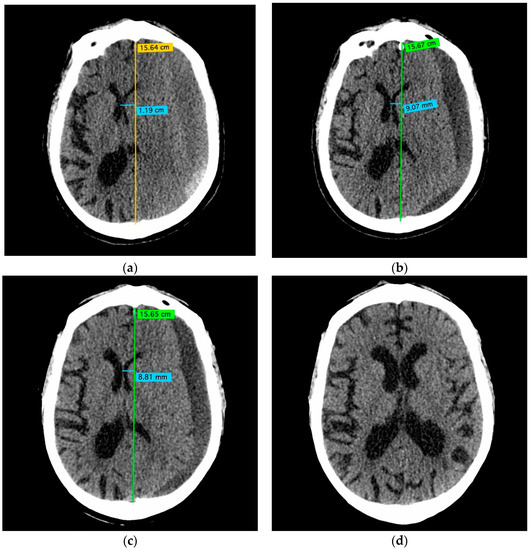

2.3. CSDH Volume Measurement

- A 70-year-old patient with left-handed CSDH and a midline shift of 12 mm, motor aphasia, and right-hand hemiparesis.

- A 42-year-old patient with bilateral CSDH that progressively increased during 1.5 months from 54 mL to 69 mL on the right-hand side and from 68 mL to 83 mL on the left-hand side, causing significant compression of both hemispheres and neurological deterioration.

- An 89-year-old patient with bilateral CSDH (no midline shift). There was no apparent connection with an antecedent head injury. However, the patient’s relatives reported that the patient did periodically fall. At the time of admission, the patient presented tetraparesis and a decreased level of consciousness.

3.4. Illustrative Cases